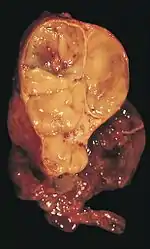

Un thymome (de thymus, en grec ancien : θυμός, « excroissance charnue »), ou tumeur épithéliale thymique, est une tumeur solide développée aux dépens du thymus, un organe intrathoracique du système immunitaire. Les thymomes atteignent plutôt l'adulte. Il en existe plusieurs sortes, et ils sont généralement asymptomatiques, mais certains sont liés à des maladies systémiques comme la myasthénie (une maladie auto-immune caractérisée par une faiblesse musculaire) ou le syndrome de Good (une défaillance du système immunitaire).

Le thymus est un organe intrathoracique, situé dans la loge thymique, dans le médiastin antérieur[3]. Cette zone est située entre les poumons, et à l'avant du cœur et des gros vaisseaux tels que l'aorte et ses branches[4]. Le thymus est constitué de deux lobes unis par le milieu, sauf à leurs extrémités supérieure et inférieure, appelées les cornes thymiques[5]. Le thymus comprend une région superficielle, appelée « cortex », et une région profonde, appelée « médulla ». Il grandit de la naissance jusqu’à la puberté, puis régresse progressivement[6].

Organe du système immunitaire[5], le thymus est spécialisé dans la maturation de certains lymphocytes, cellules du système immunitaire chargées de reconnaître et de détruire les cellules étrangères à l'organisme normal (cellules atteintes par un virus ou cellules cancéreuses, par exemple). Le cortex thymique est principalement composé de ces lymphocytes (aussi appelés thymocytes) ainsi que de quelques cellules épithéliales et mésenchymateuses[Note 2], tandis que la médulla est composée de nombreuses cellules épithéliales et quelques thymocytes[7]. C'est à partir des cellules épithéliales que se forment les thymomes[4].

Les thymomes se développent à partir des cellules épithéliales thymiques, d'où leur nom global de « tumeurs épithéliales thymiques ». Les tumeurs de la loge thymique développées à partir d'autres types de cellules ne sont pas des thymomes. Ainsi, les lymphomes atteignant le thymus ne doivent pas être considérés comme appartenant aux thymomes, de même que les tumeurs localisées dans le médiastin antérieur et développées à partir de cellules non natives du thymus (tumeur fibreuse solitaire, lipome, liposarcome, tumeurs germinales...)[45].